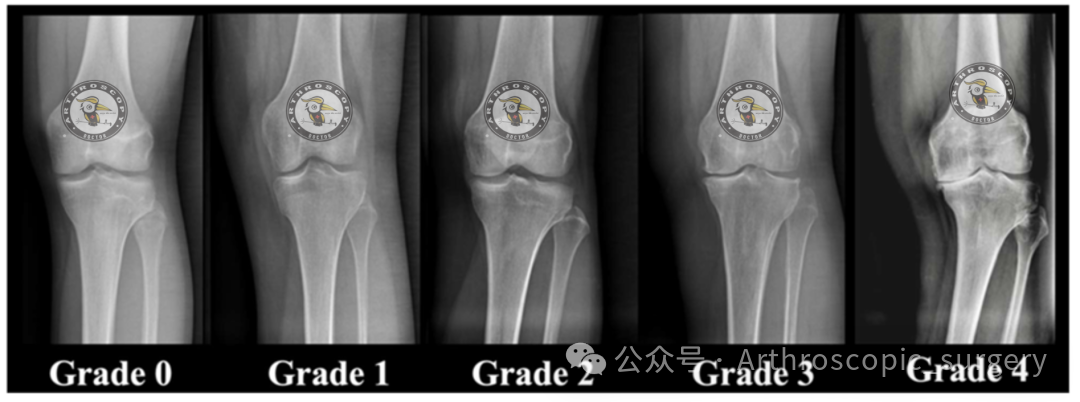

50岁以上患者,若发现无症状的MMRT(偶发性),且存在Kellgren-Lawrence 3-4级骨关节炎,或内侧间室超过50%区域出现Outerbridge 3-4级软骨磨损,可采取保守治疗。

推荐意见 22:

终末期膝骨关节炎(Kellgren-Lawrence 4级)患者应采用保守治疗方案。

Kellgren-Lawrence 3级膝骨关节炎并非MMRT修复的绝对禁忌证,但需综合评估年龄、下肢力线及其他间室受累情况。

推荐意见 40:

终末期膝骨关节炎(Kellgren-Lawrence 4级)患者不宜进行MMRT手术修复。